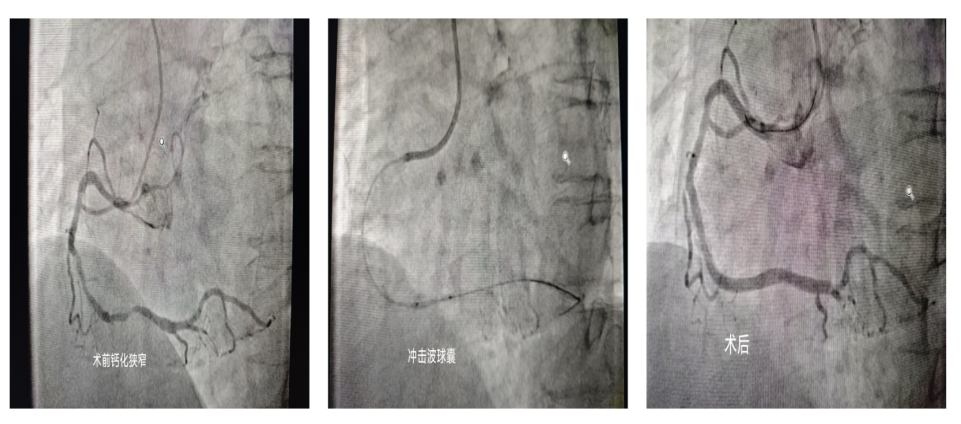

术前术后对比